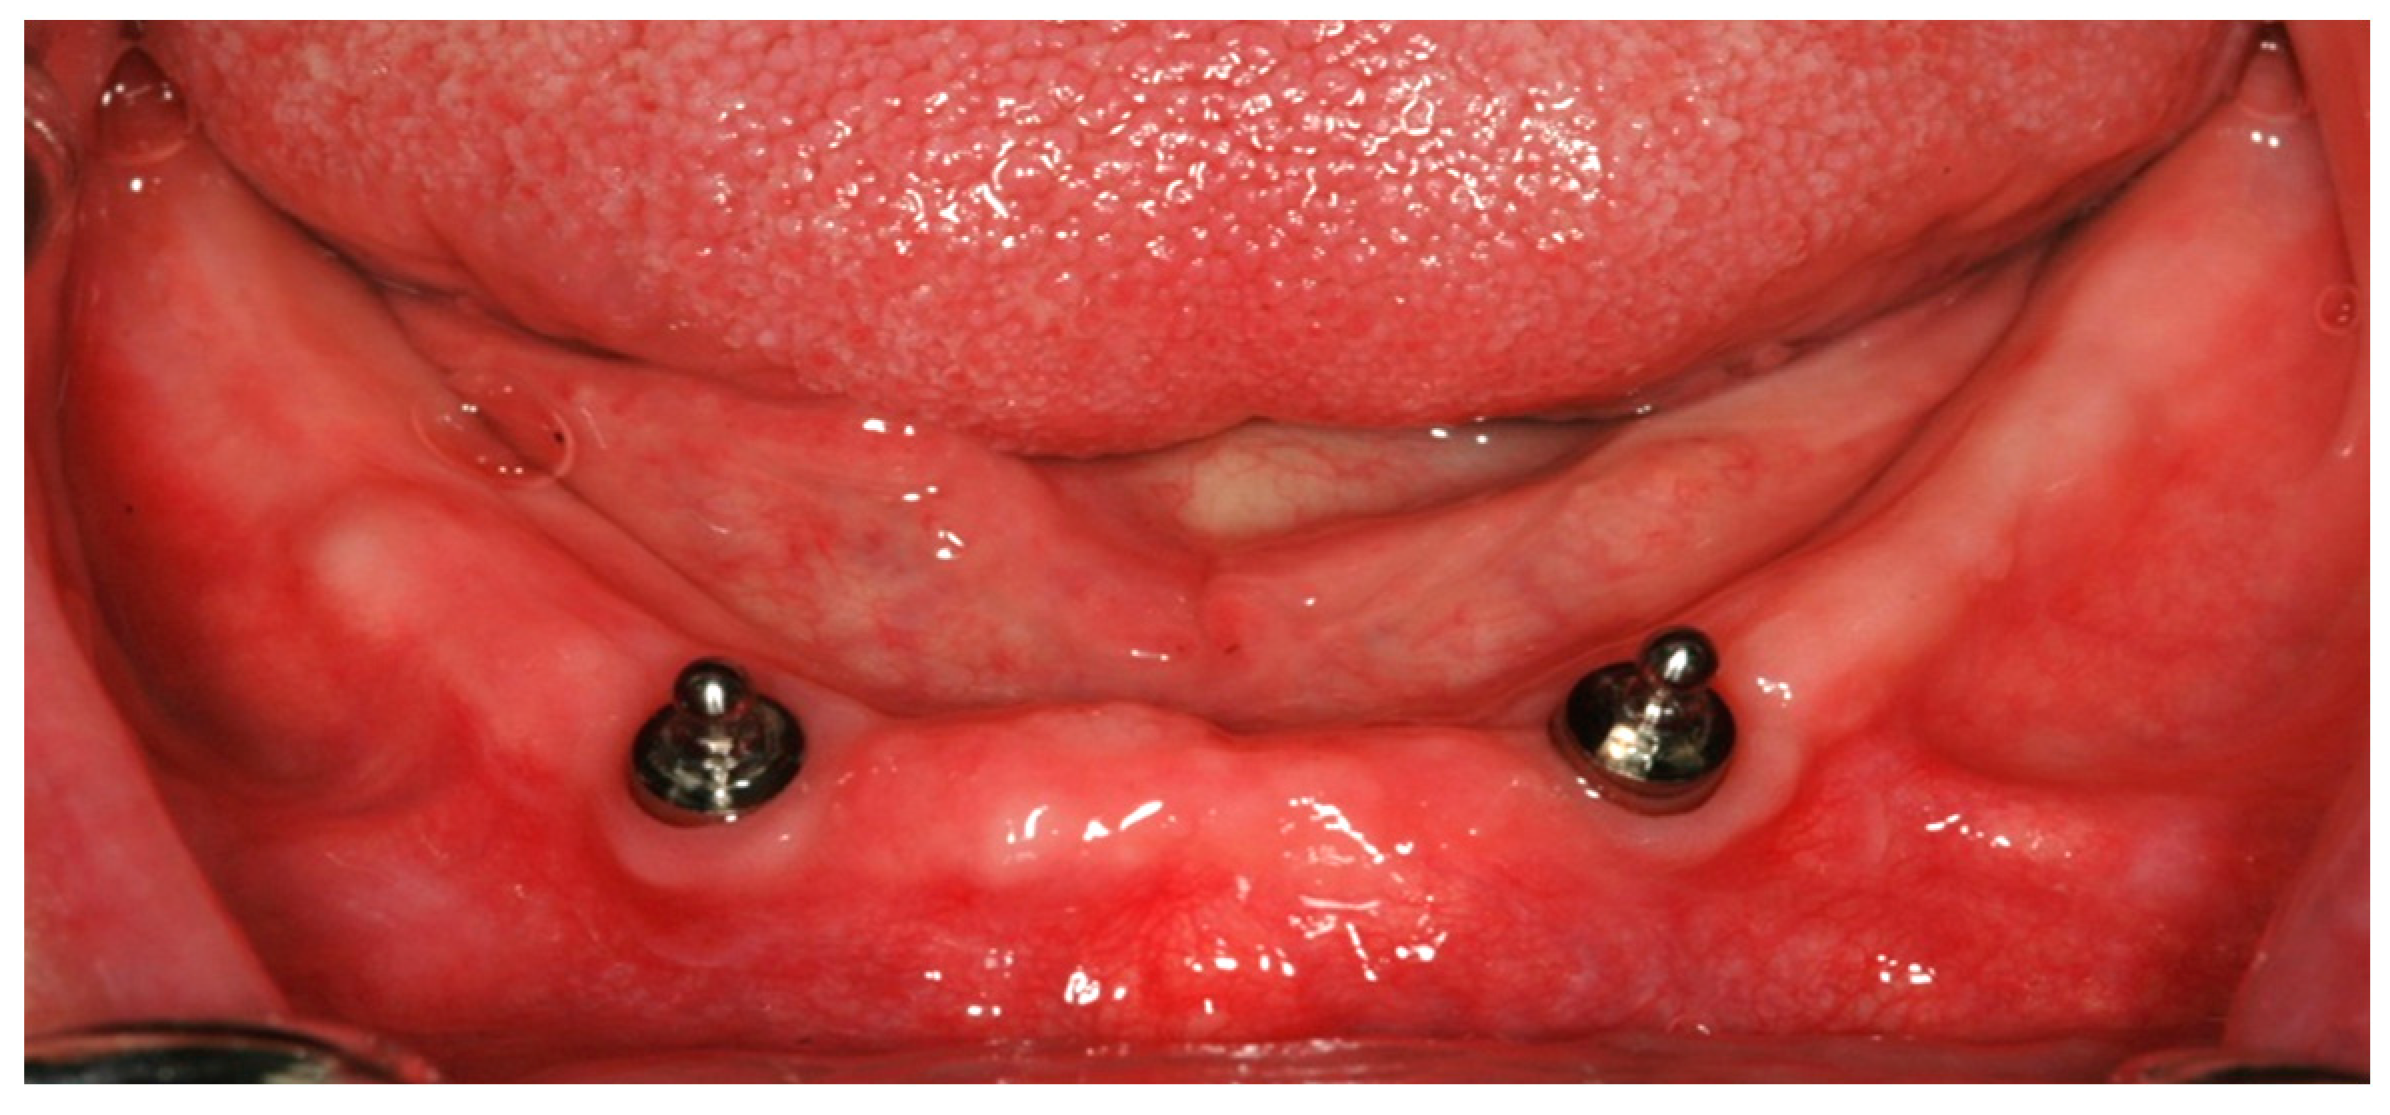

2.3. Surgical Treatment

2.4. Prosthetic Treatment